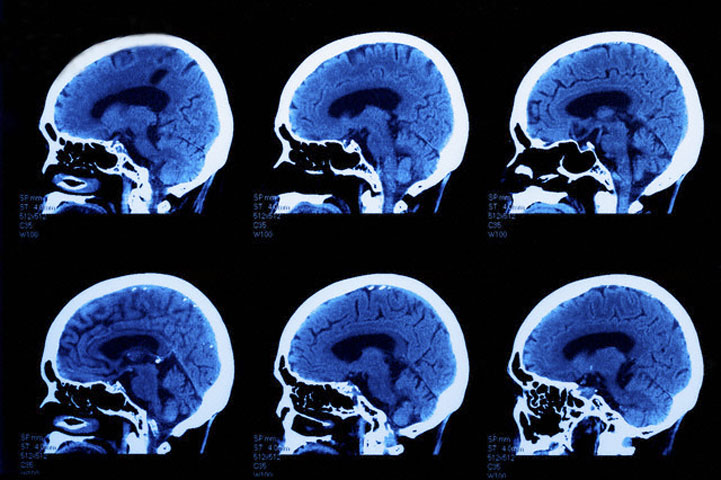

КТ, или компьютерная томография мозга – это новейший метод диагностики организма, в частности мозга, которое происходит при помощи рентгенологического исследования на специальном аппарате – мультиспиральном компьютерном томографе. Данный метод позволяет получить наиболее точное изображение мозга головы без каких либо изменений.

Обследовать нервную систему можно любыми способами, даже используя старый метод с использованием иглы и молоточка. Но мы живем в век технологий, да и медицина шагнула далеко вперед. Томография мозга позволяет подтвердить поставленный врачом диагноз и то, от чего он возник. Есть несколько разновидностей компьютерной томографии, и все они позволяют просканировать мозг с получением фотографии мозга в виде нескольких слоев, причем расстояние между слоями составляет всего несколько миллиметров.

Если проводят компьютерную томографию, при которой используют рентген, то визуальную картинку получают только после того, как провели просвечивание головы рентгеновскими лучами. В результате такого просвечивания получают черно-белую картинку, так называемую томограмму. Метод дает много информации, но у него есть недостаток – пациент подвергается сильному излучению.

Одним из сложнейших методов компьютерной томографии является позитронно-эмиссионная вариация томографии мозга. Такое обследование позволяет получить цветное изображение и рассмотреть головной мозг в мельчайших подробностях, начиная от заболеваний сосудов и заканчивая крошечными опухолями.